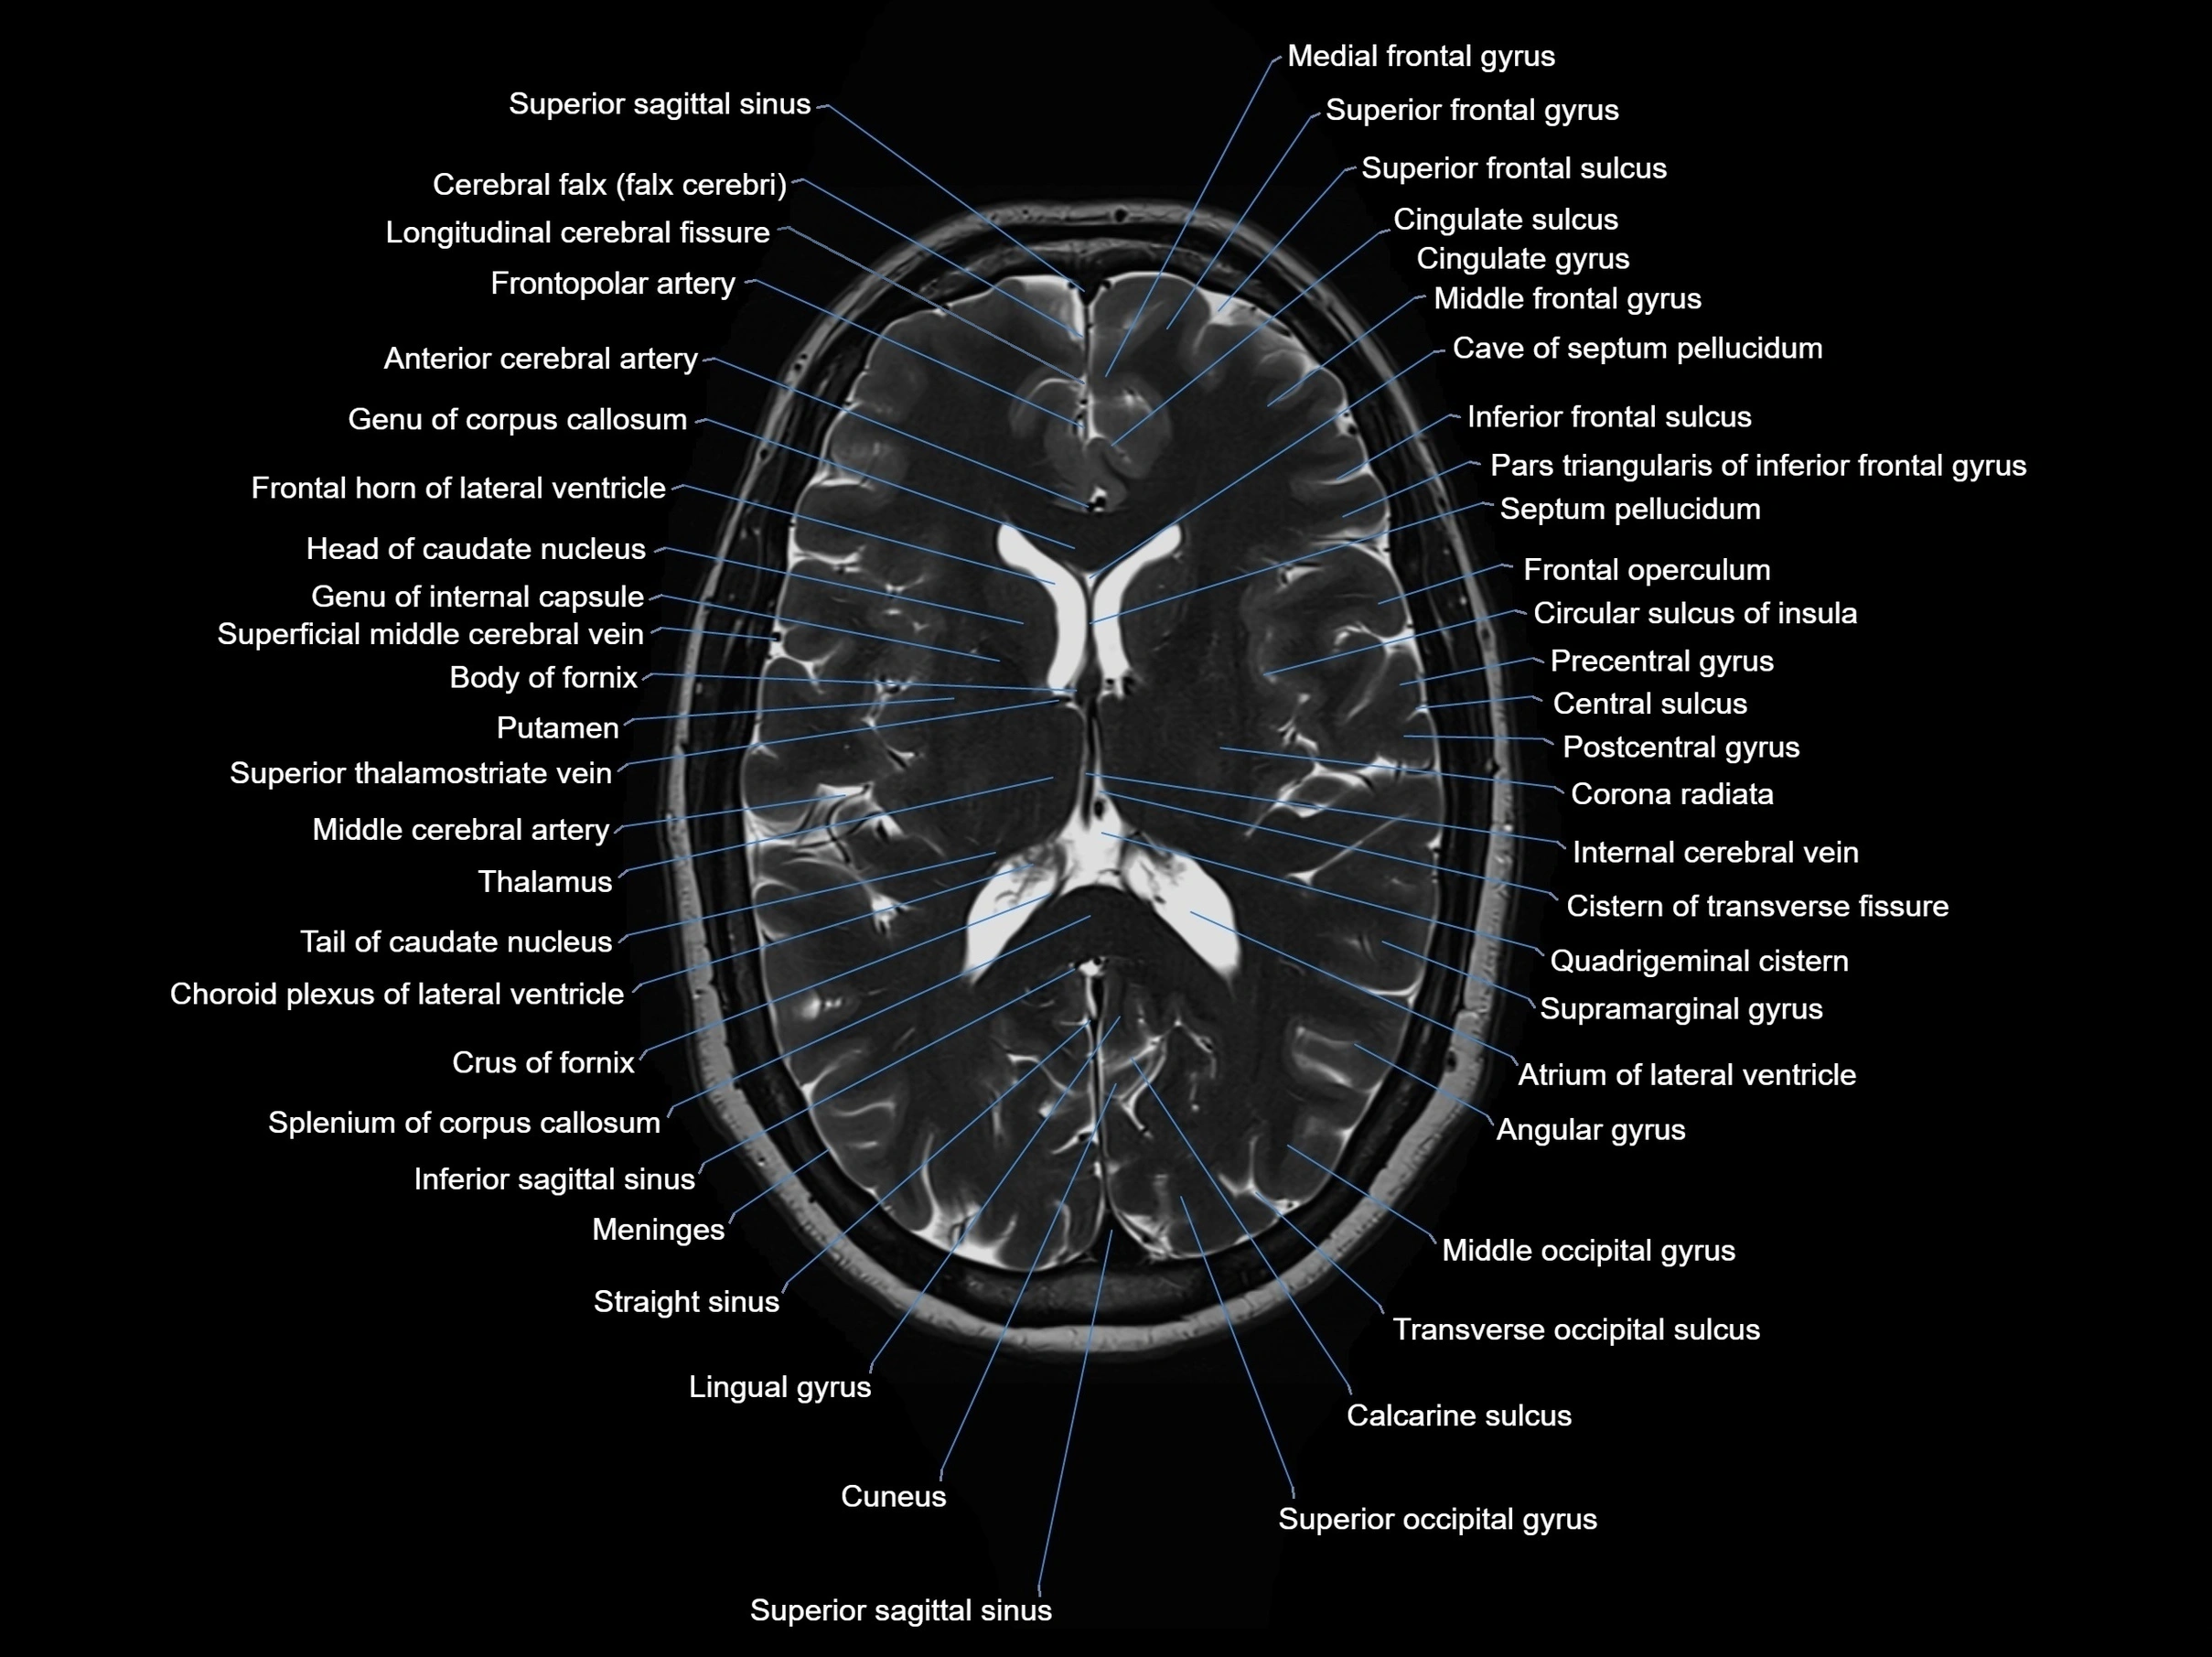

MRI images